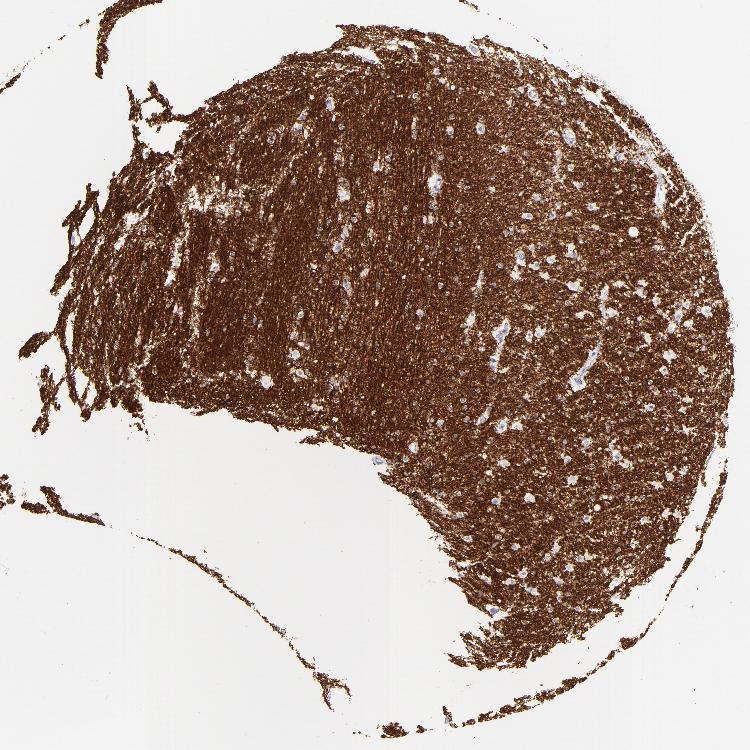

HIPPOCAMPUS - Antibody stainingi

Antibody staining in the annotated cell types in the current human tissue is reported as not detected, low, medium, or high, based on conventional immunohistochemistry profiling in selected tissues. This score is based on the combination of the staining intensity and fraction of stained cells.

Each image is clickable and will lead to virtual microscopy that enables deeper exploration of all samples and also displays staining intensity scores, fraction scores and subcellular localization as well as patient and tissue information for each sample.

Antibody HPA023266Antibody HPA023278Antibody HPA023280Antibody HPA023338Antibody CAB002672

Glial cells HighMediumMediumHighHigh

Neuronal cells Not detectedNot detectedNot detectedNot detectedNot detected